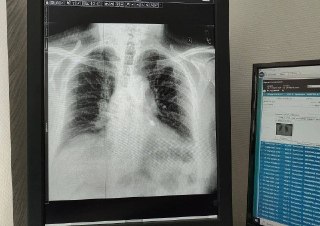

Мужчина лечил зубы в частной клинике. В процессе лечения стоматологический бур попал в дыхательные пути. Пациент обратился в Мытищинскую больницу — рентген показал, что инструмент застрял в левом бронхе.

Врач-эндоскопист Мария Юрченко с помощью специального инструмента зафиксировала бур и аккуратно извлекла его. Повреждения тканей удалось избежать, пациент спасён.